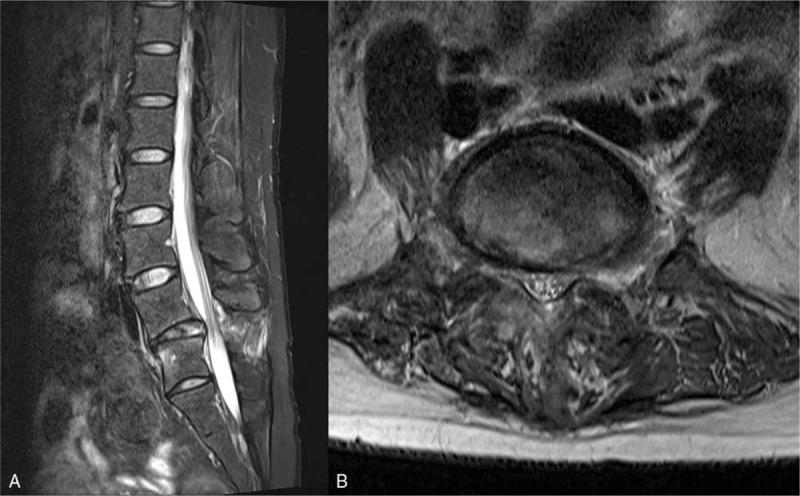

Initial imaging studies revealed a fracture of the left L5 superior articular process with a posterior ligament complex (PLC) injury. Subsequent radiographs showed the locked facet dislocation with kyphotic changes.

初始影像学检查显示L5左侧上关节突骨折伴后韧带复合体(PLC)损伤。随后的X线片显示小关节脱位并伴有脊柱后凸改变。